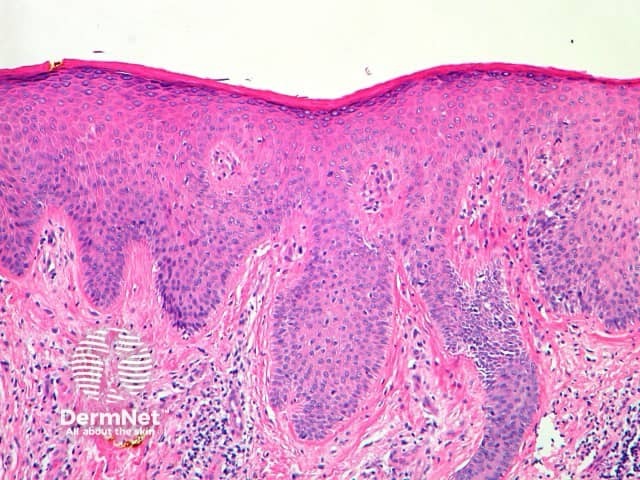

The histological features of lichen planus are:

Pathology of lichen planus